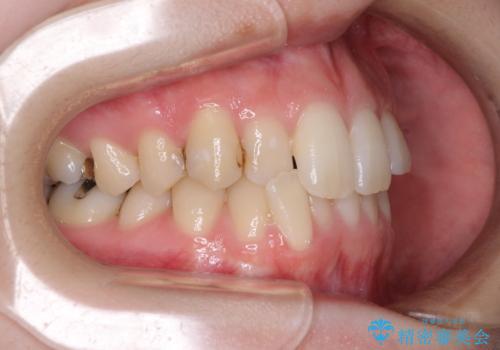

- 前歯のデコボコをクロスバイトを気にして来院された患者様です。

上顎骨の横幅が狭く、上下ともに内側に倒れ込んだ混み合った歯列となっていました。

急速拡大装置により上顎骨を側方に拡大し、ワイヤー装置により歯列を整えることとしました。

矯正治療後には、目立つ銀歯と隣接するむし歯をセラミックインレーにて修復治療することとしました。